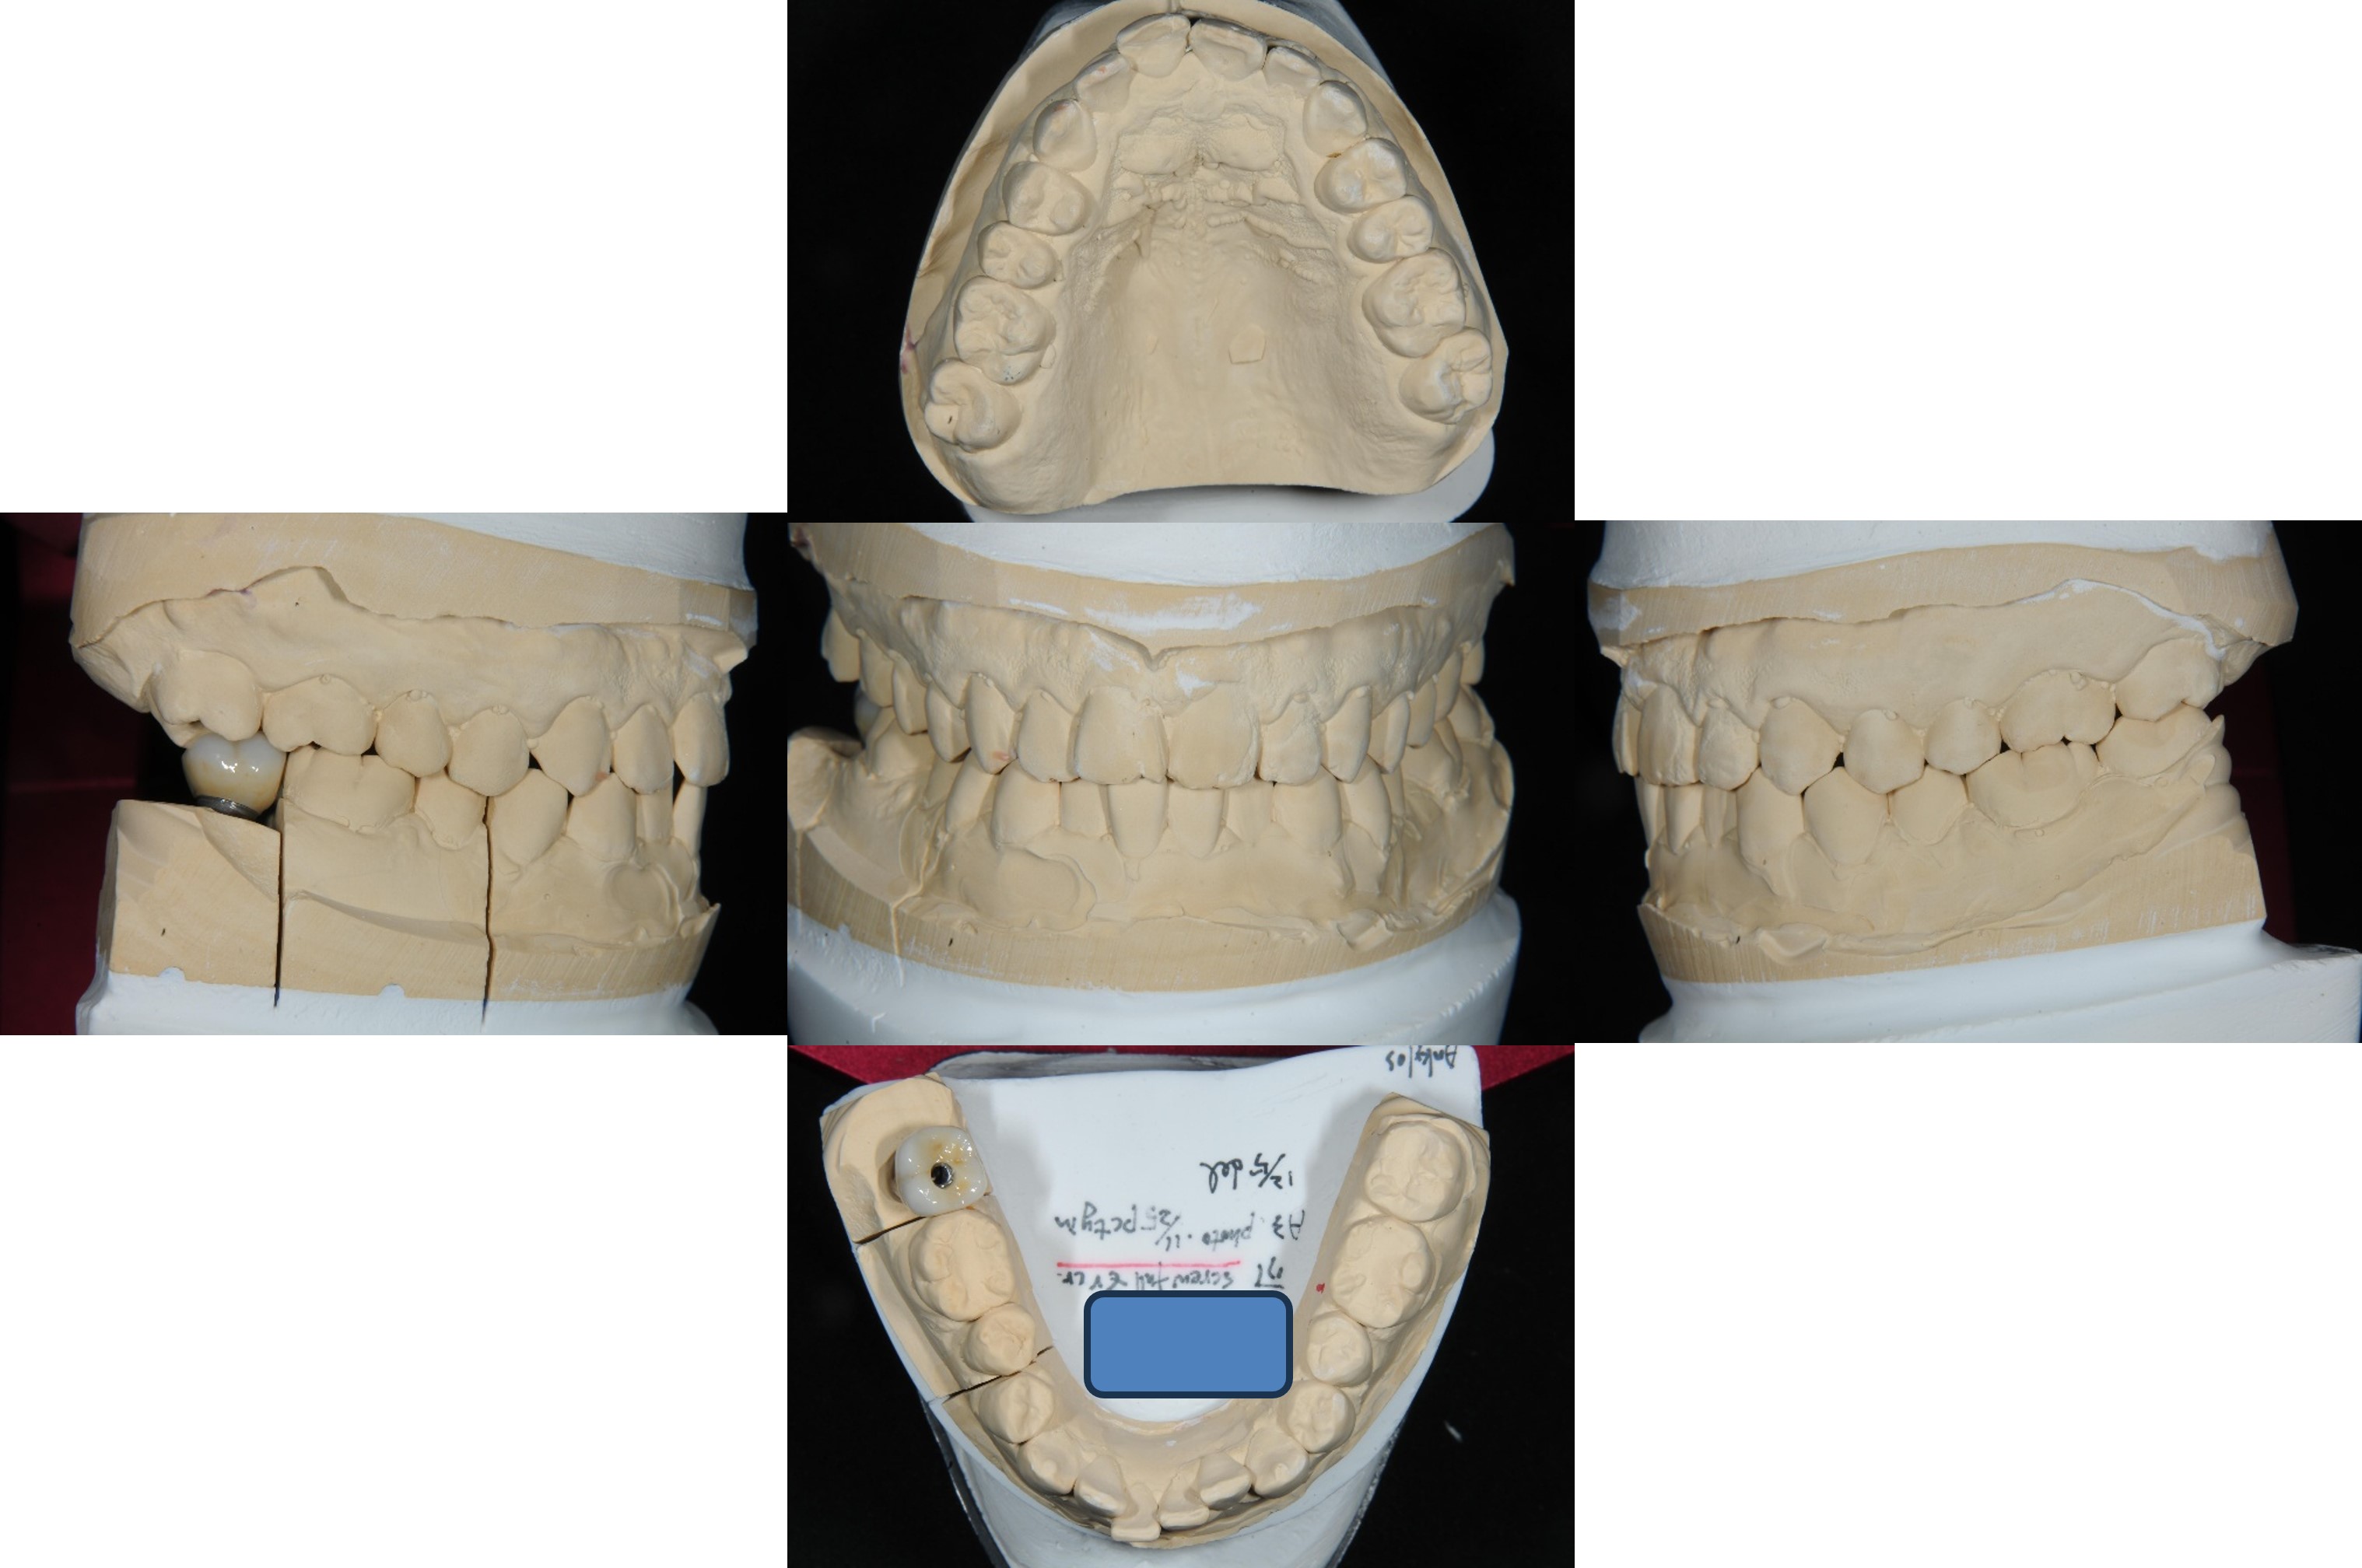

植牙規畫模擬

手術模板

面弓轉移,上咬合器

咬合器上製作瓷牙